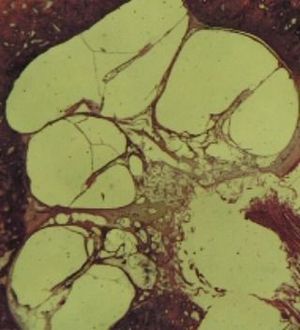

This is a histological picture showing hydrops in the cochlea indicating meniere's disease. It is a disease charactereized by a triad of sensorineural hearing loss, vertigo and tinnitus. Causes of this disease could be head trauma or syphilis which will result in dilation of membranous labrynth due to excess endolymph in the cochlea. Treatment is non-medically by using low salt diet and avoidance of alcohol, nicotine, and caffeine consumption. Medical treatment is thiazide, antihistamines, and anticholinergics. Surgical treatment is labyrinthectomy.